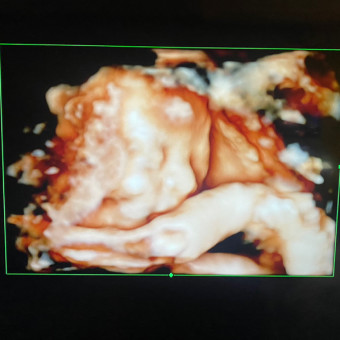

Taylor's Baby Registry

Taylor Bombinski & Kahlif Marshall

Brown Deer, WI

September 13, 2025

Help us welcome our baby girl! 💕